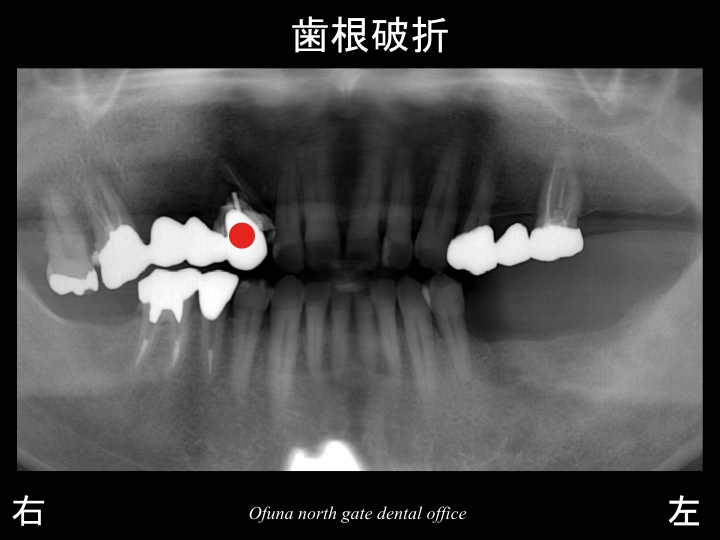

ところが、少し前から上顎の左側の奥歯で噛むことができなくなってきました。

上顎左側が歯根破折 していたのです。

歯根破折 についてはこのブログでも良く紹介する内容です。

歯根破折 している場合、抜歯となることがほとんどです。

また 診査の結果、さまざまな問題が起こっていました。

その一つが、噛み合わせのズレです。

下顎の右側の奥歯が欠損した状態で長期間放置してしまったため、

噛み合う上顎の歯が挺出してきたのです。

以下のレントゲンは、噛み合わせのズレを表示したものです。

青線は、正常な状態を表した状態です。

以下の赤線は、現在の患者様の状態です。

上顎の歯が挺出し、噛み合わせが斜めになっているのが分かるかと思います。